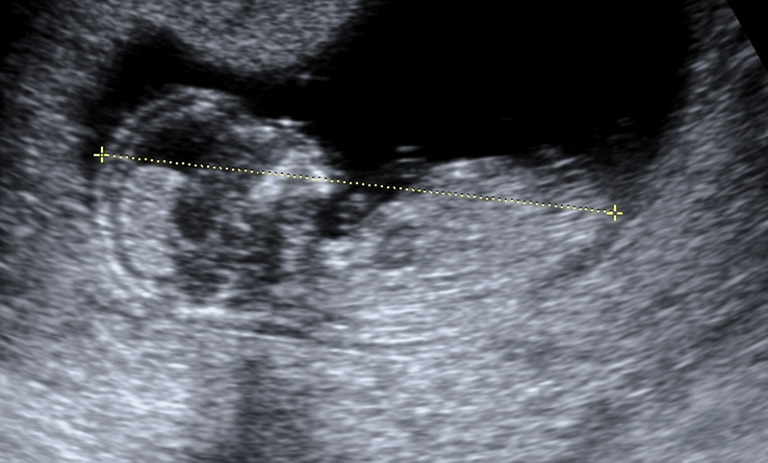

ultrason ölçümleri